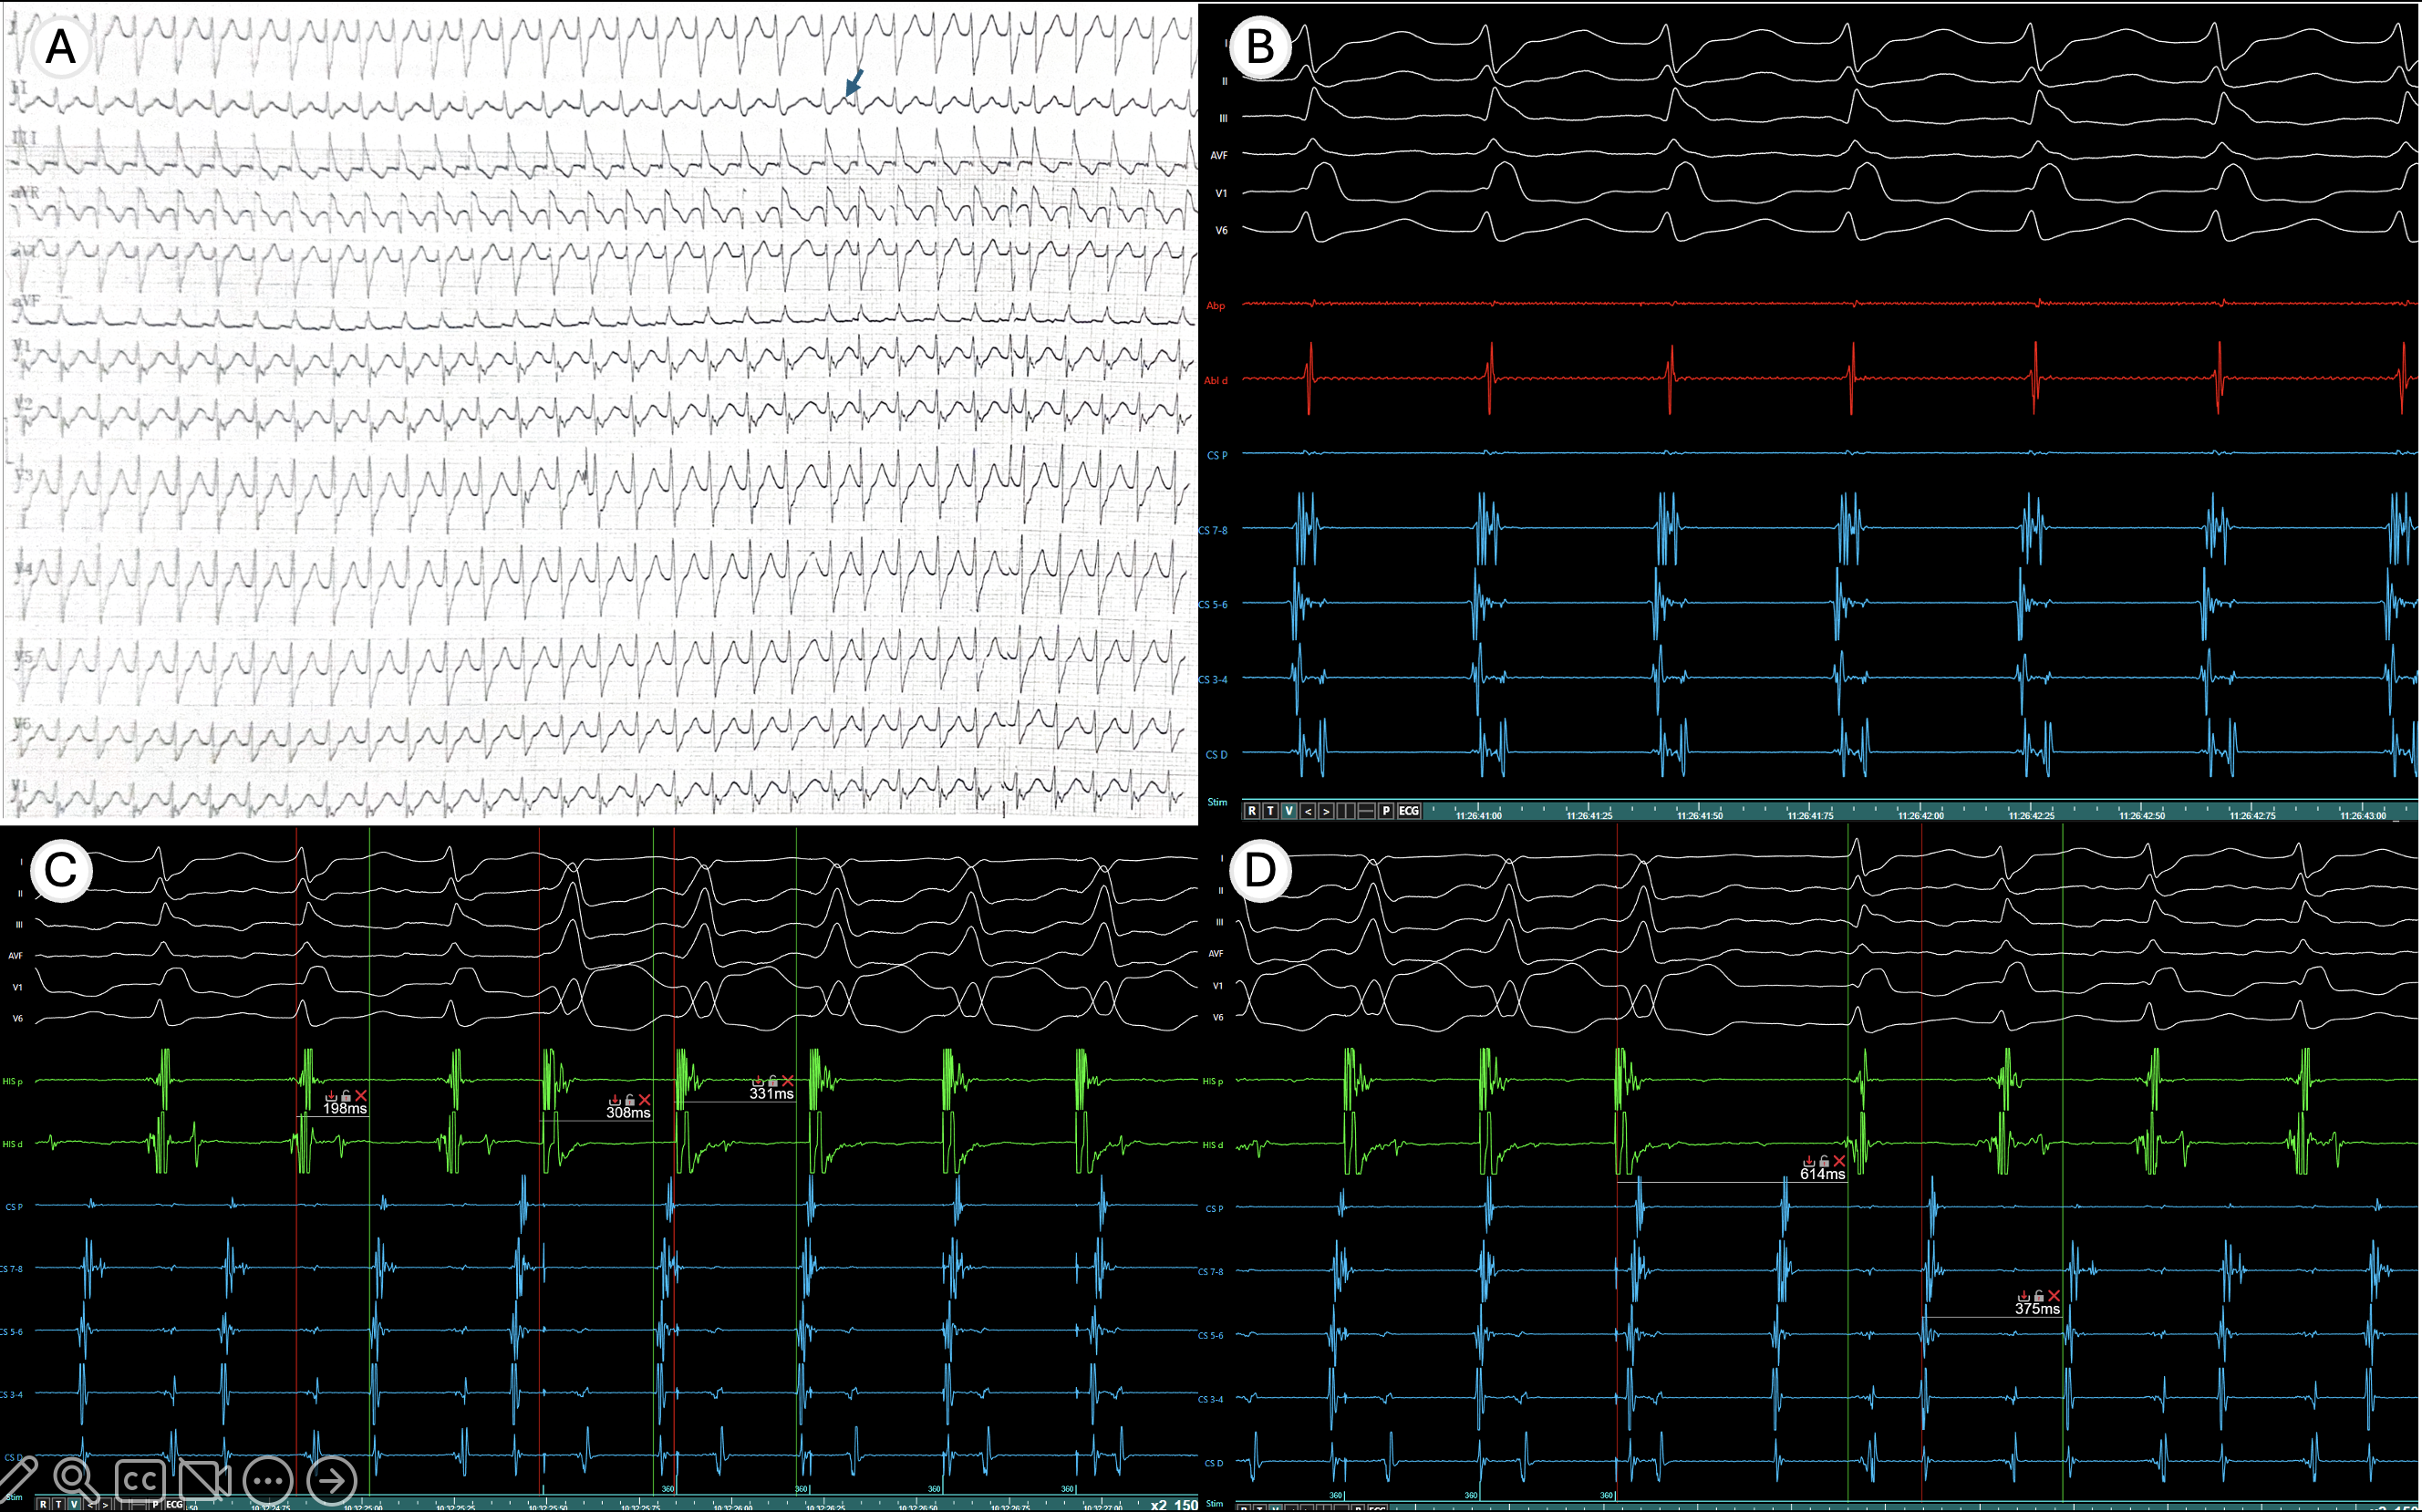

Background In patients with long RP tachycardias, the differential diagnosis be...